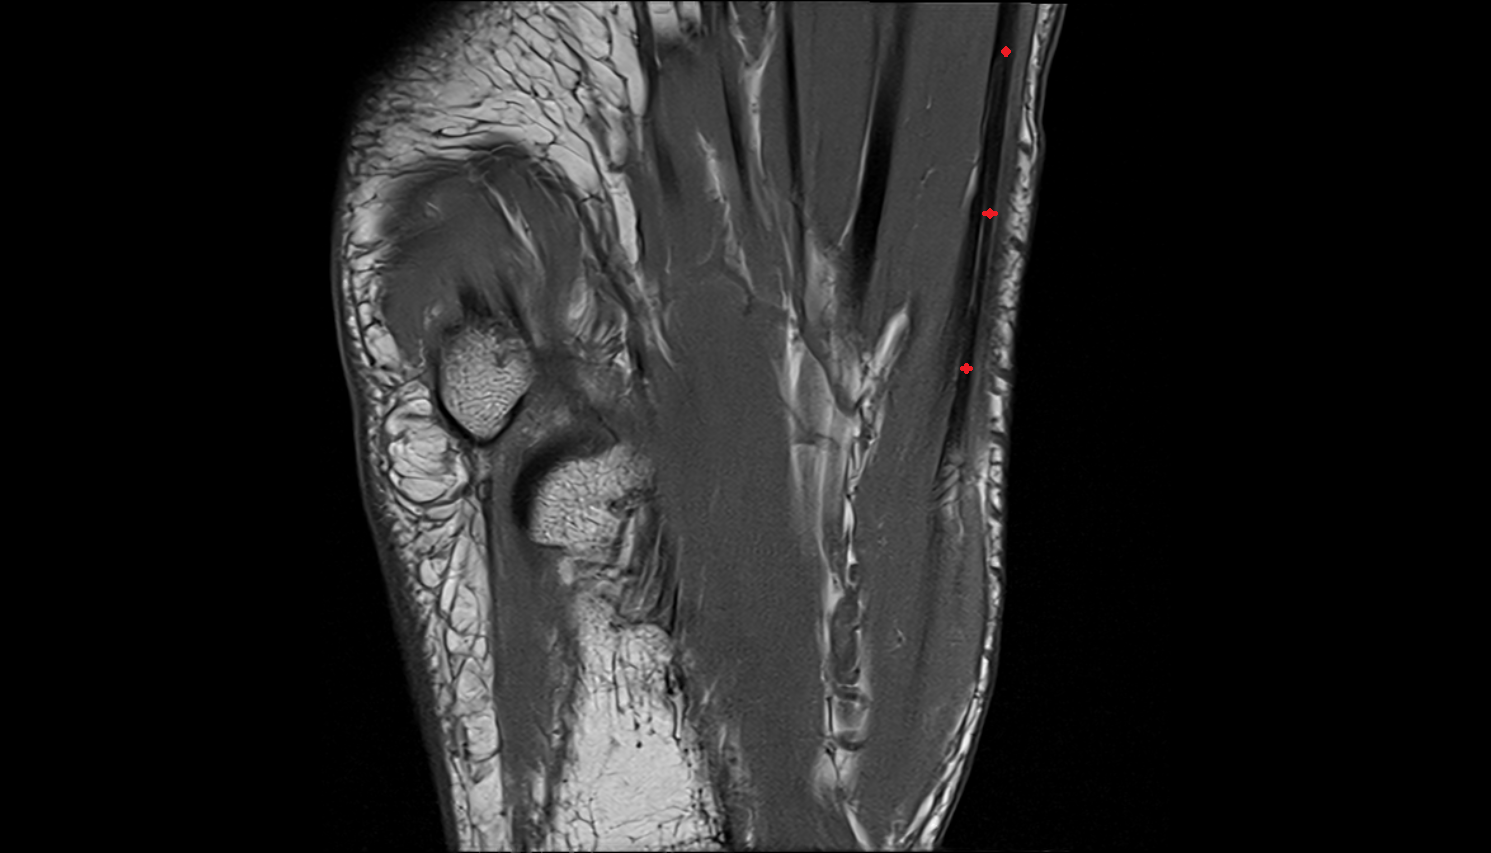

- Talus

- Head of talus

- Body of talus

- Neck of talus

- Calcaneus

- Ankle joint

- Talocalcaneal joint